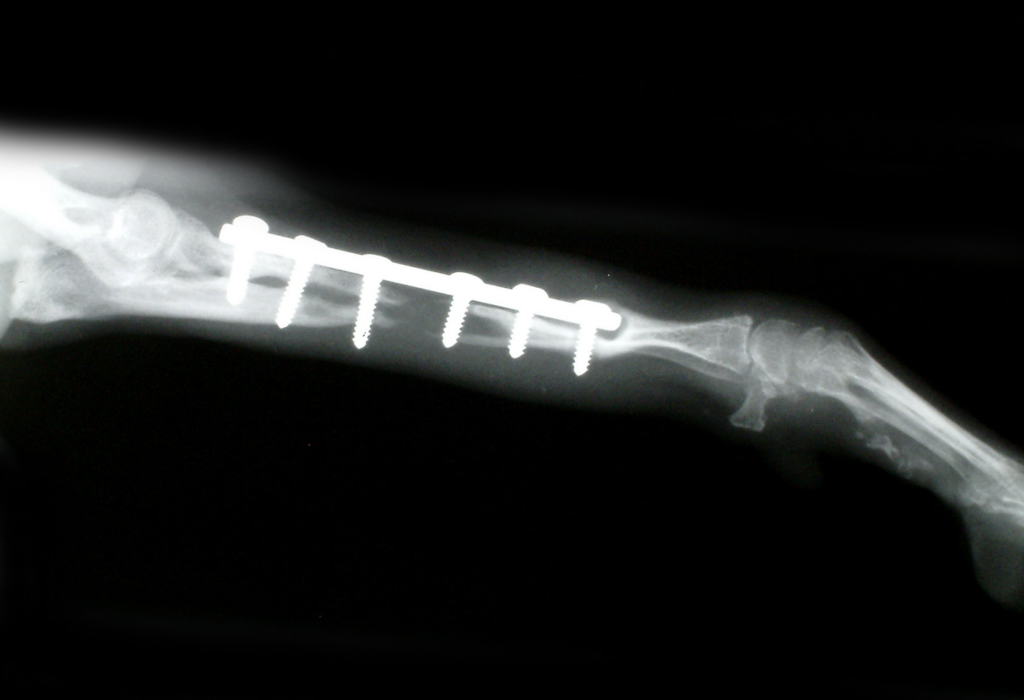

「骨折ですね。手術をして金属プレートで固定しましょう。」

上手くいく訳のない手術をして骨折が治らなければ

その犬の治癒力のせいにされたり・・

【目からウロコの骨折の予防と治療】

・従来の骨折治療法

・新しい骨折治療法